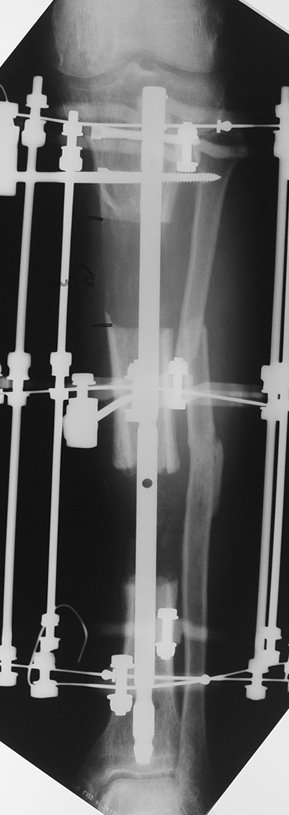

Uygun radikal debridman tüm nekrotik kemik ve yumuşak dokuların çıkartılmasını gerektirir, ve sıklıkla uzuvda instabiliteye neden olur. Kalan kemik ve yumuşak doku defektinin bir şekilde fiksasyonu ve rekonstrüksiyonu gereklidir. İlizarov’un ortaya koyduğu distraksiyon osteogenezi yöntemi, kaynamanın elde edilmesi, deformitenin düzeltilmesi, bacak boy eşitsizliğinin giderilmesi ve segmental defektlerin rekonstrükte edilmesi için başarıyla kullanılmaktadır.

Eksternal fiksatör ile geçen süre (eksternal fiksasyon indeksi), gereken distraksiyon miktarına bağlıdır ve bu süre boyunca bazı komplikasyonlarla karşılaşılabilir. Distraksiyon dönemi sona erdikten sonra, distraksiyon süresinin iki katını aşan konsolidasyon döneminde hastalar eksternal fiksatörü zorlukla tolere edebilirler. Yeterli konsolidasyon sağlanmadan eksternal fiksatör çıkartılırsa ise kırıklar, deformite ve kısalık oluşabilir. Hastanın fiksatör ile birlikte geçirdiği sürenin azaltılması ve böylece hasta konforunun ve aktivite düzeyinin arttırılması için intramedüller çivi üzerinden uzatma yöntemi uygulanmaktadır. Bu yöntemde distraksiyon dönemi sona erdiğinde kemiğin içindeki çivi statik olarak kilitlenmekte ve eksternal fiksatör çıkartılmaktadır. Stabilizasyon intramedüller çivi tarafından sağlandıktan sonra konsolidasyon dönemi gerçekleşmektedir. Bu şekilde hem eksternal fiksatörün uzun süre kalmasından hem de erken çıkartılmasından kaynaklanan komplikasyonların önüne geçilmektedir.